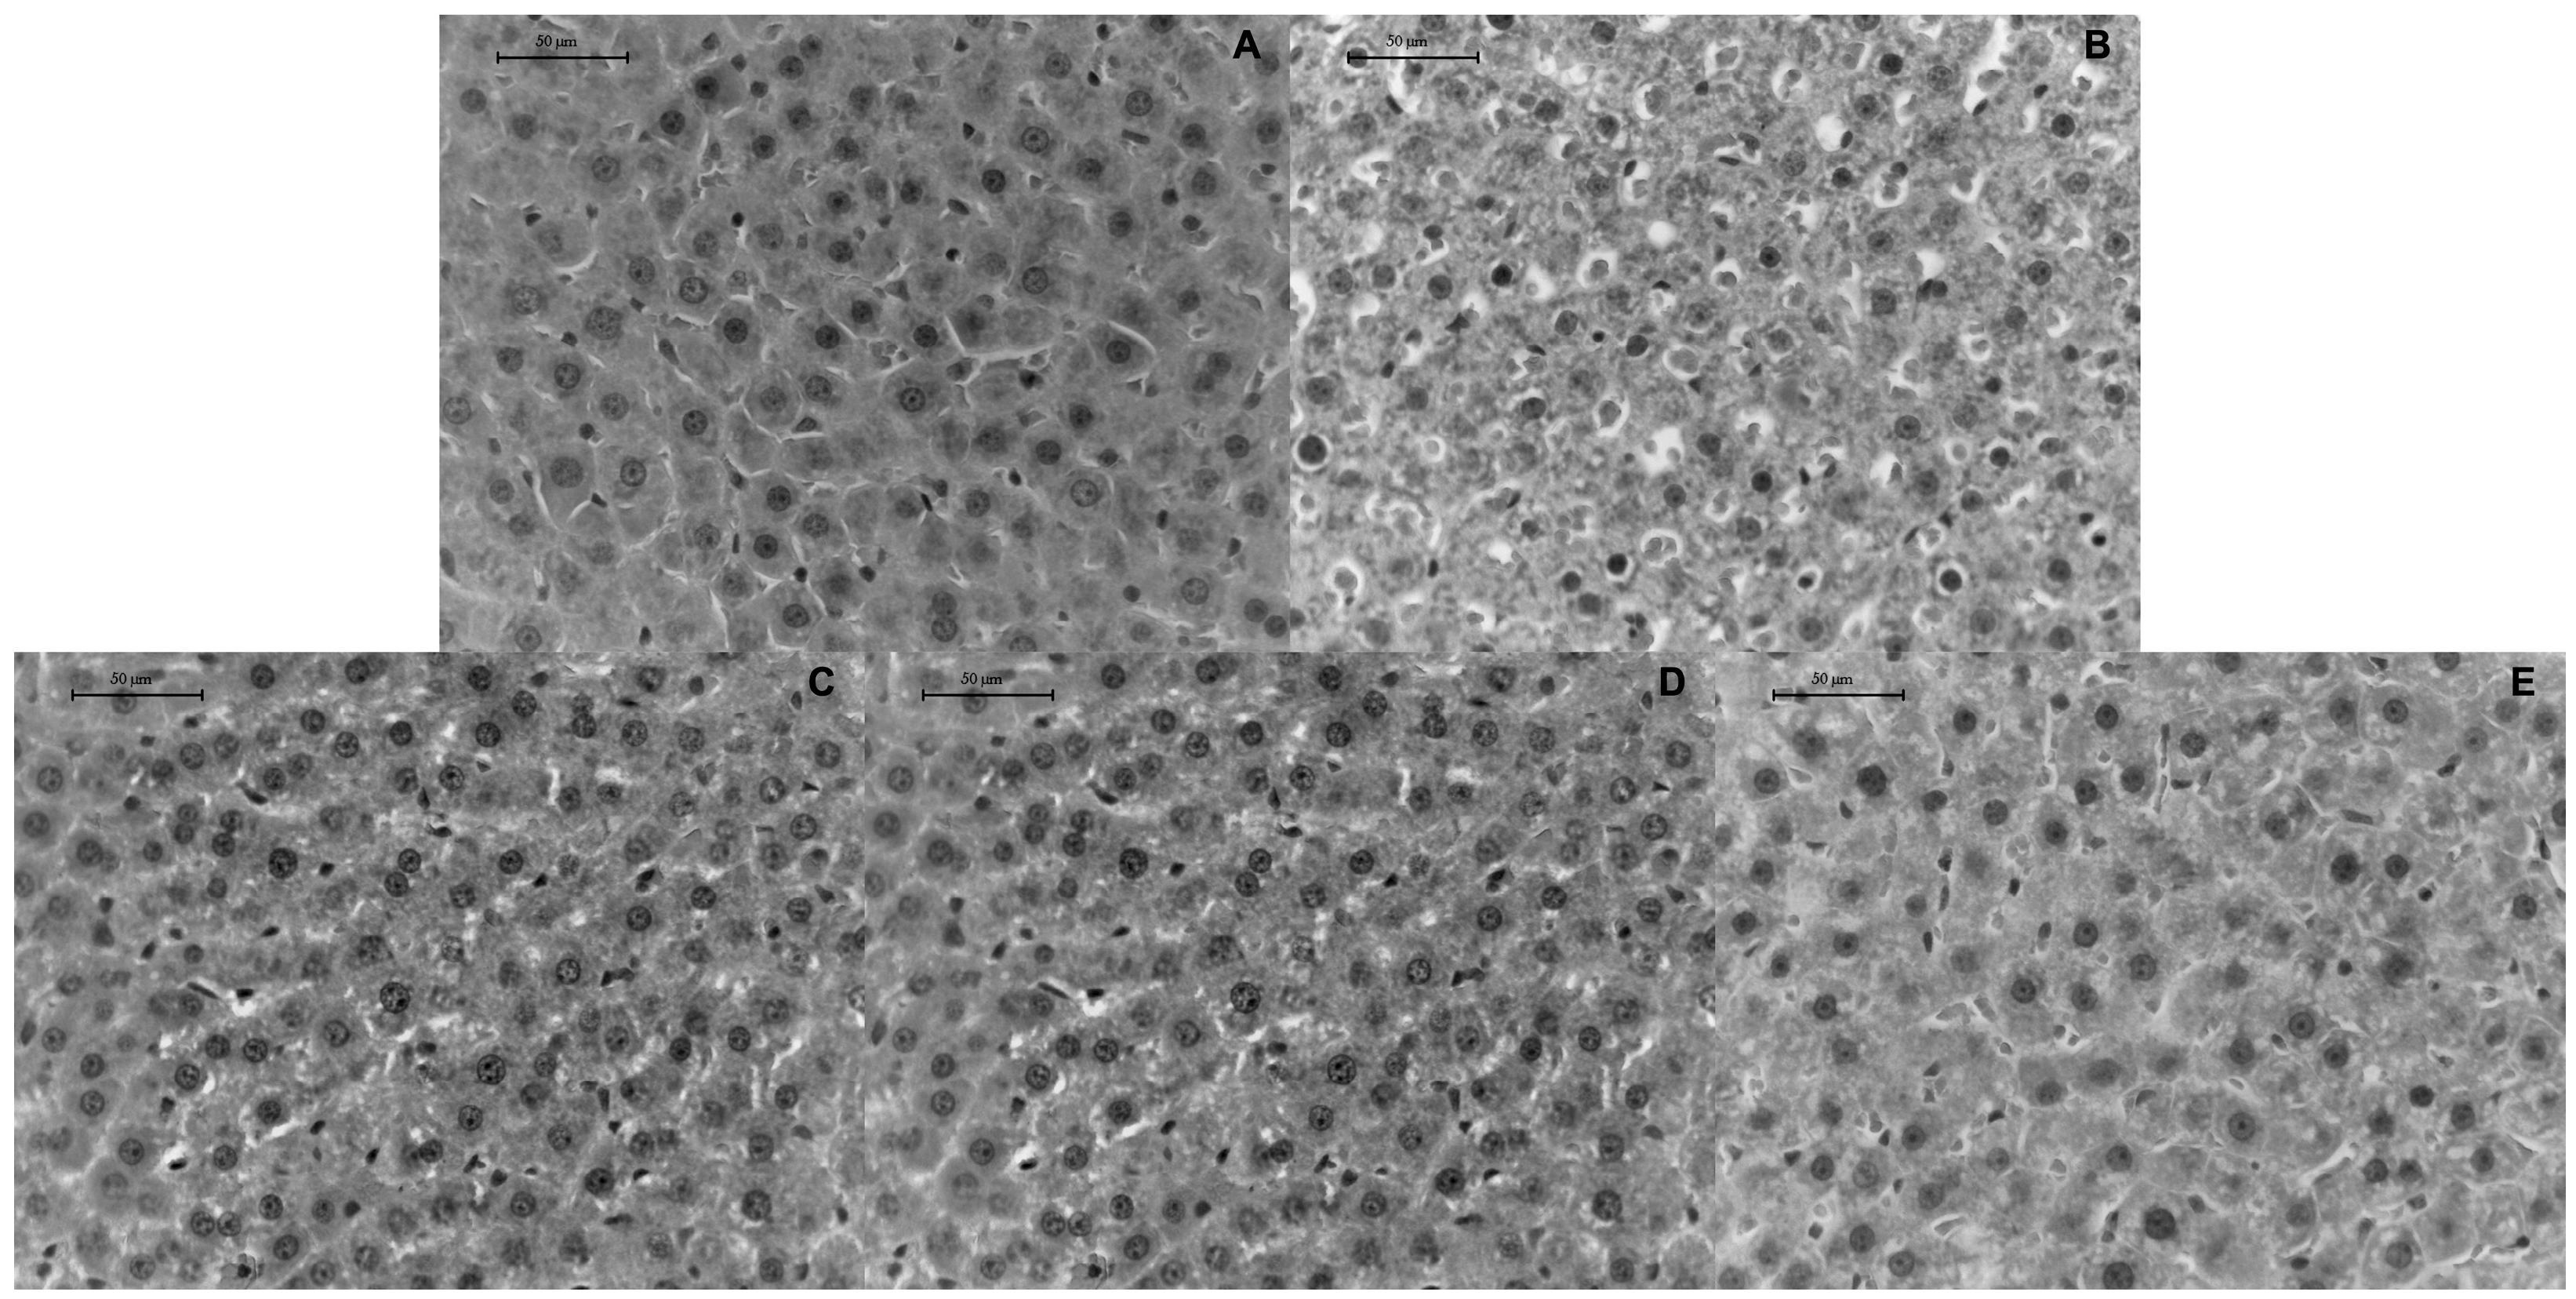

3.3. RBR Supplementation Attenuates Hepatic Steatosis in Late-Stage T2DM Rats